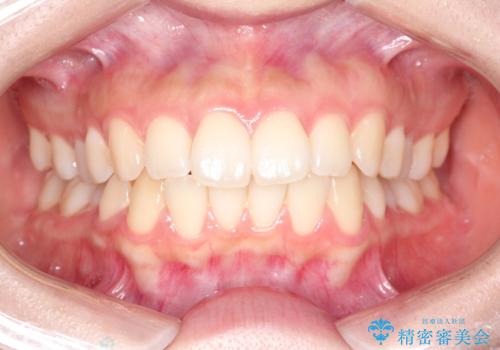

20代男性 ハーフリンガルによる抜歯矯正

- 2年5ヶ月

骨格的に上顎より下顎が後退しているため、少々上の前歯が内側に倒れこんでいる印象になった仕上がりとなっております。

来年の4月から就職とのことで、学生の間に矯正治療を終了でき満足されていました。